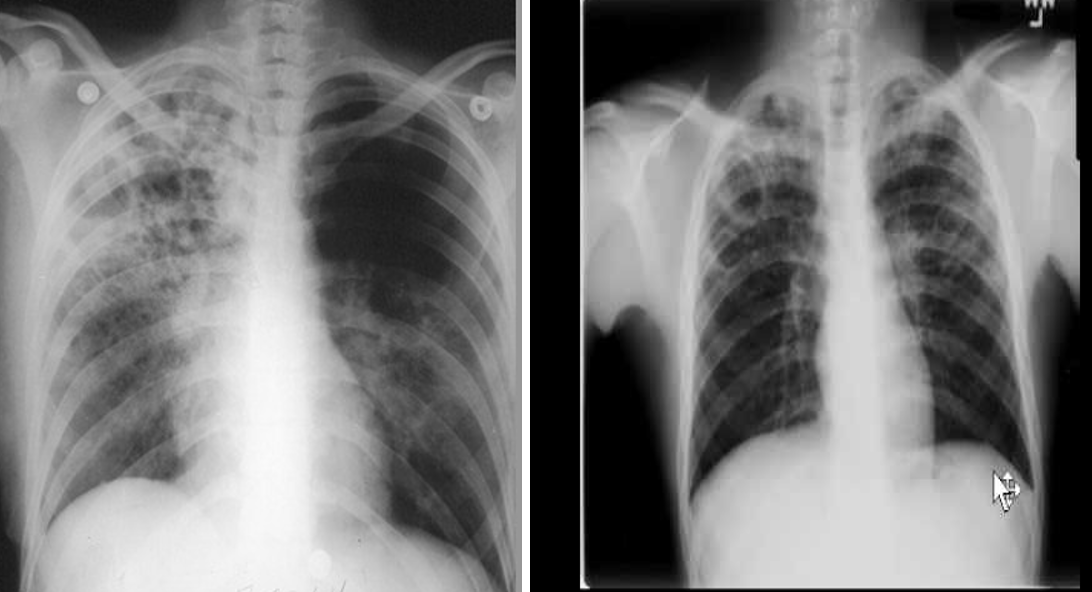

comparision with Pneumonia